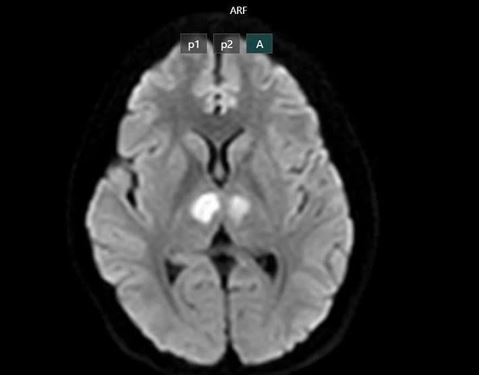

Hệ lụy tổn thương não do nhiễm độc chất cấm sau sử dụng sản phẩm giảm cân không rõ nguồn gốc .Ảnh: BỘ Y TẾ

Cụ thể, một cô gái 21 tuổi ở Hà Nội hiện bị tổn thương não nặng (đang còn điều trị) sau khi sử dụng sản phẩm sức khỏe mua trên TikTok dẫn đến nhiễm độc Sibutramine. Cô vốn khỏe mạnh, đang dùng sản phẩm tự mua này gần một tháng (bao bì hoàn toàn bằng tiếng nước ngoài, không rõ là thuốc hay thực phẩm chức năng) thì đột ngột bất tỉnh, không sốt, không co giật. Kết quả MRI cho thấy tổn thương vùng đồi thị hai bên não. Hay một phụ nữ 37 tuổi đi cấp cứu sau khi sử dụng cà phê giảm cân; uống đến lần thứ 4 thì bị khó thở, lạnh toát, háo nước, hạ thân nhiệt đột ngột; kết quả xét nghiệm xác định sản phẩm chứa Sibutramine.